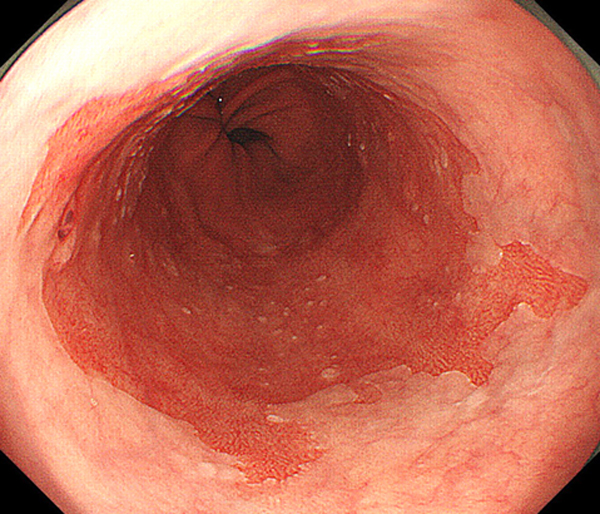

内視鏡所見と病理組織像の1対1対応が可能な症例を公募いたします。主にLSBEに発生した早期癌(HGDを含む)を対象としますが、興味深い症例であればSSBE癌でも結構です。採否は世話人へご一任ください。

特に、本邦では極めて稀なlong segment Barrett’s esophagus(LSBE)から発生した早期癌は、診断に難渋する場合も多く、欧米ではランダム生検による検出が標準的とされています。背景のBarrett食道もろとも全体を内視鏡切除+ラジオ波焼灼する欧米と異なり、ESDで内視鏡的な局所切除が基本の本邦では、存在診断+範囲診断(特に水平)を的確に行うことが不可欠です。

そのためには、一流の病理医による組織学的診断とエキスパート内視鏡医による拡大内視鏡像との一対一対応を徹底的に行うことで、『本来、見えないであろう拡大所見の先にある組織構築像が診えてくる』所まで内視鏡診断レベルを上げていく必要があります。その実現には、一対一対応を追究した症例(特にLSBE発生例)1例でも多く経験するしかありません。本研究会でBarrett食道腺癌(LSBE発生早期病変)を共に学び、拡大内視鏡像の一歩先を診るスキルを習得しましょう!一人でも多くの皆様のご参加をお待ちしています。

私は、Barrett食道癌はHGDも含め、内視鏡による存在診断、範囲診断が可能と信じて来ました。しかし最近、NBI拡大観察を併用しても側方範囲診断が不可能なLSBE症例を経験しました。診断技術を向上させるためには、多くの症例を診るしかありません。そこで、Barrett食道に造詣の深い先生方に世話人をお願いし、Barrett食道研究会を立ち上げることに致しました。全国からLSBE症例を集め、内視鏡的、組織学的診断に迫りたいと思います。皆様のご参加をお待ち致します。